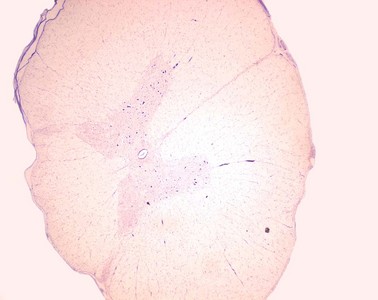

Präparat 26: Multipolare Nervenzellen, Rückenmark (Schwein), Nissl-Färbung

Substantia grisea, von der weißen Substanz (Substantia alba) umschlossener Teil des Rückenmarks, der die Perikaryen der Nervenzellen und das Neuropil (ein Geflecht von Nerven- und Gliazellfortsätzen mit vielen Synapsen) umfasst. Im Querschnitt des Rückenmarks hat sie die charakteristische Schmetterlingsform.

Nervenzellen (Neurone) sind Zellen mit Fortsätzen, die sich hinsichtlich ihrer Länge, Struktur und Funktion unterscheiden. Das morphologische und trophische Zentrum einer Nervenzelle ist das Perikaryon (synonym: Soma, Zellleib), in dem sich der Zellkern befindet. Die Fortsätze der Nervenzellen sind die Dendriten, über die Signale von anderen Nervenzellen empfangen werden, und das Axon, das die Erregung der Nervenzelle in Form von Aktionspotentialen weiterleitet. Das Axon kann eine beträchtliche Länge erreichen und von einer Markscheide umhüllt sein (entsprechend werden markhaltige und marklose Axone unterschieden). Die Dendriten besitzen keine Markscheide. Von einem Perikaryon können ein oder mehrere Dendriten abgehen. Neurone mit mehreren Dendriten werden als multipolare Nervenzellen bezeichnet. Um den komplexen Aufbau der Nervenzellen im Lichtmikroskop zu erkennen, müssen unterschiedliche Färbetechniken verwendet werden.

Hier wurde ein Querschnitt durch das Rückenmark mit dem Farbstoff Creyslviolett behandelt (Nissl-Färbung), der basophile Zellbestandteile intensiv blau darstellt. Zum Studium der Nervenzellen suchen wir die Vorderhörner der schmetterlingsförmigen grauen Substanz des Rückenmarks auf, in denen die Perikaryen der großen motorischen Nervenzellen (Motoneurone) liegen, die bereits in dieser Übersicht als intensiv blau gefärbte Punkte zu erkennen sind.